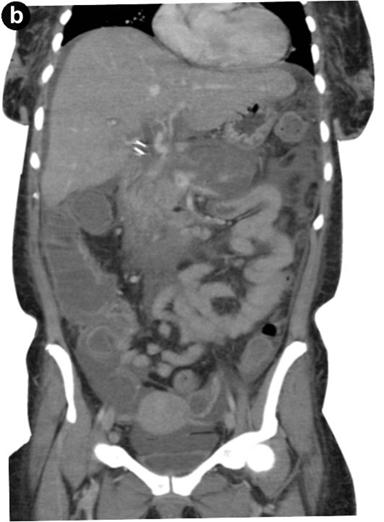

At the GI clinic 11 days post-discharge, the patient appeared toxic, weak, and complained of mild, diffuse abdominal pain and dizziness. She was found to be hypotensive (blood pressure: 85/45 mmHg and tachycardic (heart rate: 134 beats/min). On day 2 after her readmission, she spiked a fever of 102.8°F (39.3°C) and had several episodes of non-bilious vomiting. Upright abdominal radiograph showed no free air or bowel obstruction. Her serum lipase increased from 99 U/L to 427 U/L (reference range: 8-78 U/L) within 48 hours (Figure 2), while her serum amylase was only elevated on day 2 of readmission (240 U/L; reference range: 40-130 U/L). Abdominal ultrasound (US) was negative for biliary duct disease. CT scan of the abdomen revealed enlarged and nonenhancing body and tail of the pancreas consistent with pancreatic necrosis (Figure 3). Cerebrospinal fluid analysis was positive for active shedding of CMV virus (12,811 copies/mL) without signs of meningitis. The patient’s serum anti-CMV IgG antibodies were elevated (118.8 EU/mL; reference range: 0-8 EU/mL), while anti-CMV IgM antibodies were negative. No other virus was detected in the blood or cerebrospinal fluid.

Figure 3. Coronal (a.) and sagittal (b.) CT scan of the abdomen showing enlarged and non-enhancing body and tail of the pancreas consistent with pancreatic necrosis. |